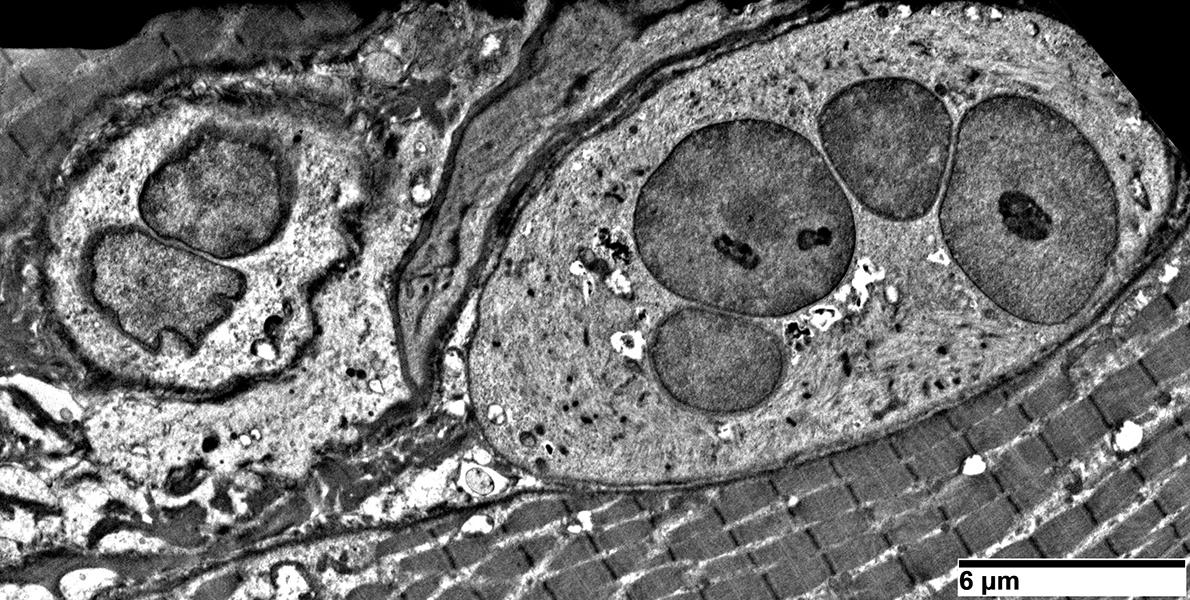

Pyknotic nuclear clumps: Ultrastructure

- Ultrastructure: 1; 2